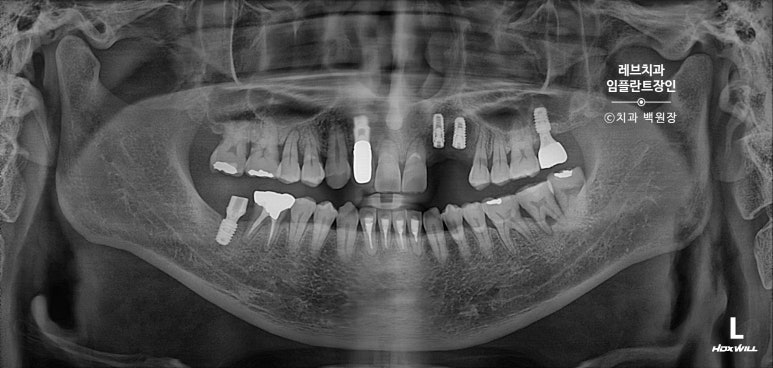

치과용 파노라마 사진을 보시면, 아주 짧은 뿌리만이 남아있는 것을 보실 수 있어요..

고개를 돌려서 보면, 뿌리만 있는 치아들이 몇개 보이고...

치아 목부위 (치경부)에 충치가 있는 치아들도 여러개 보여요.